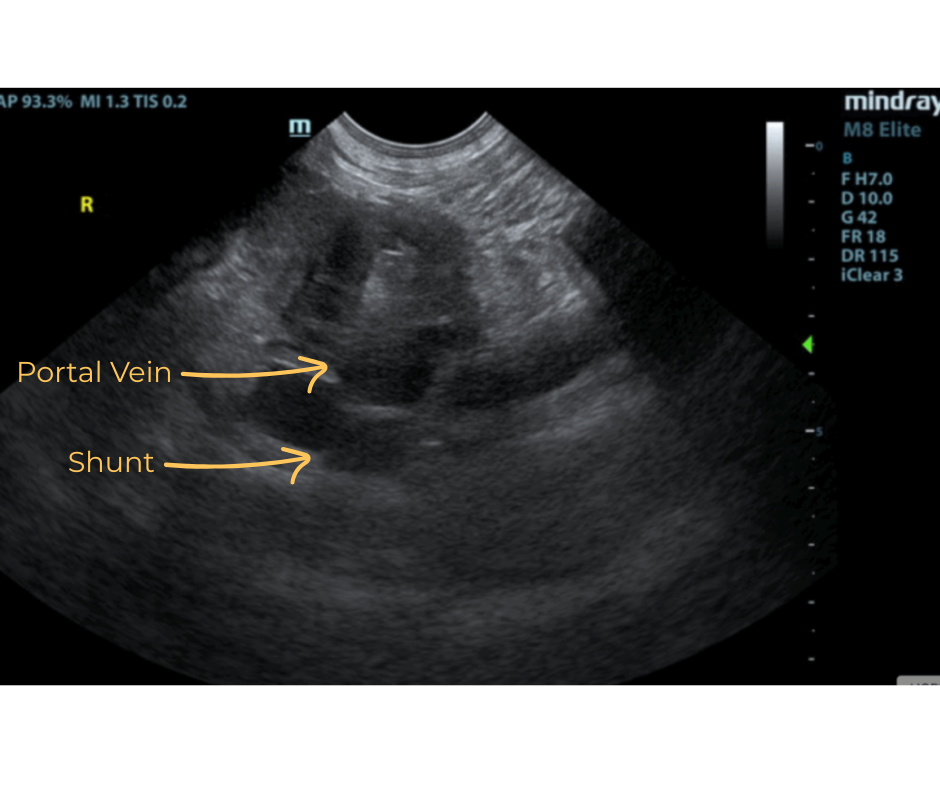

The liver was subnormal in size. The mid dorsal liver in this patient revealed an abnormal intrahepatic branch of the portal vein. This is most consistent with central divisional shunt. However, this should be further evaluated with CT. The gallbladder and common bile duct were unremarkable.

- Intrahepatic shunt – suspect central divisional or right divisional shunt

- Suspected Intrahepatic Shunt

Ultrasound can identify a small liver, abnormal vessels, altered portal vein/vena cava ratio, altered portal vein/aorta ratio, renomegaly, and urolithiasis. Identification of an IHPSS with an experienced operator has a sensitivity of 95-100%. IHPSS tend to have a large diameter and they are outlined by the liver parenchyma making them easier to identify. CT scan is used for cases that are unable to be identified using ultrasound and to correctly identify the origin and end point of the shunt for surgical planning.